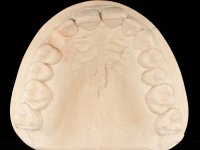

Female patient, 43 years old, non-smoker. Showed an edentulous space in the upper right canine area, resulting from tooth 1.3 impaction. The space had a mesio-distal diameter reduced to the normal size of the upper canine. This is consistent with the presence in the arch of the deciduous canine up to two years ago). Orthopantomography allows clearly view of tooth 1.3 impaction.The patient has a thick gingival phenotype and tolerable oral hygiene.

The proposed treatment results from the limitations imposed by the patient, who refused an orthodontical pull of the canine into the edntulous space, and was unwilling to extract the impacted canine and place an implant in the zone of 1.3. Thus, the confection of a Maryland Bridge was proposed, with a Zr infrastructure and two retainers. The mesial retainer would be bonded to the palatal face of the tooth 1.2 and the distal retainer was to be bonded to the palatal wall of tooth 1.4.

To define the dental zone to be covered by the Maryland bridge retainers, the patient was asked to perform maximum intercuspidation movements, and the contact points were marked with articular paper. Tooth preparation of the interproximal surfaces was made, to create a prosthetic insertion axis. It was sought that the mesio-distal diameter at the incisal level was equal to the diameter mesio-distal at the cervical level, that is to say, the interproximal walls were parallelized. Tooth preparation was done with fine grain diamond drills, and later polishing was done with abrasive discs. Color information was collected even before confection of the impression, to avoid dehydration of the arcade. Definitive impression was made using wash technique impression with silicone of heavy and regular consistency, both with fast setting, and a working plaster model was prepared in the lab. A laboratory scanner was used to scan the working model, and later, the infrastructure for the Maryland bridge was made using a CAD-CAM process. Ceramic was placed on this subframe. A ceramic adhesive was applied to the internal surface of the wings and connectors, which would enable bonding to the adjacent teeth. The adhesive bridge was bonded in the mouth following the conventional bonding technique. After bonding, the protrusion and laterality movements were carefully checked to avoid undesirable contacts.